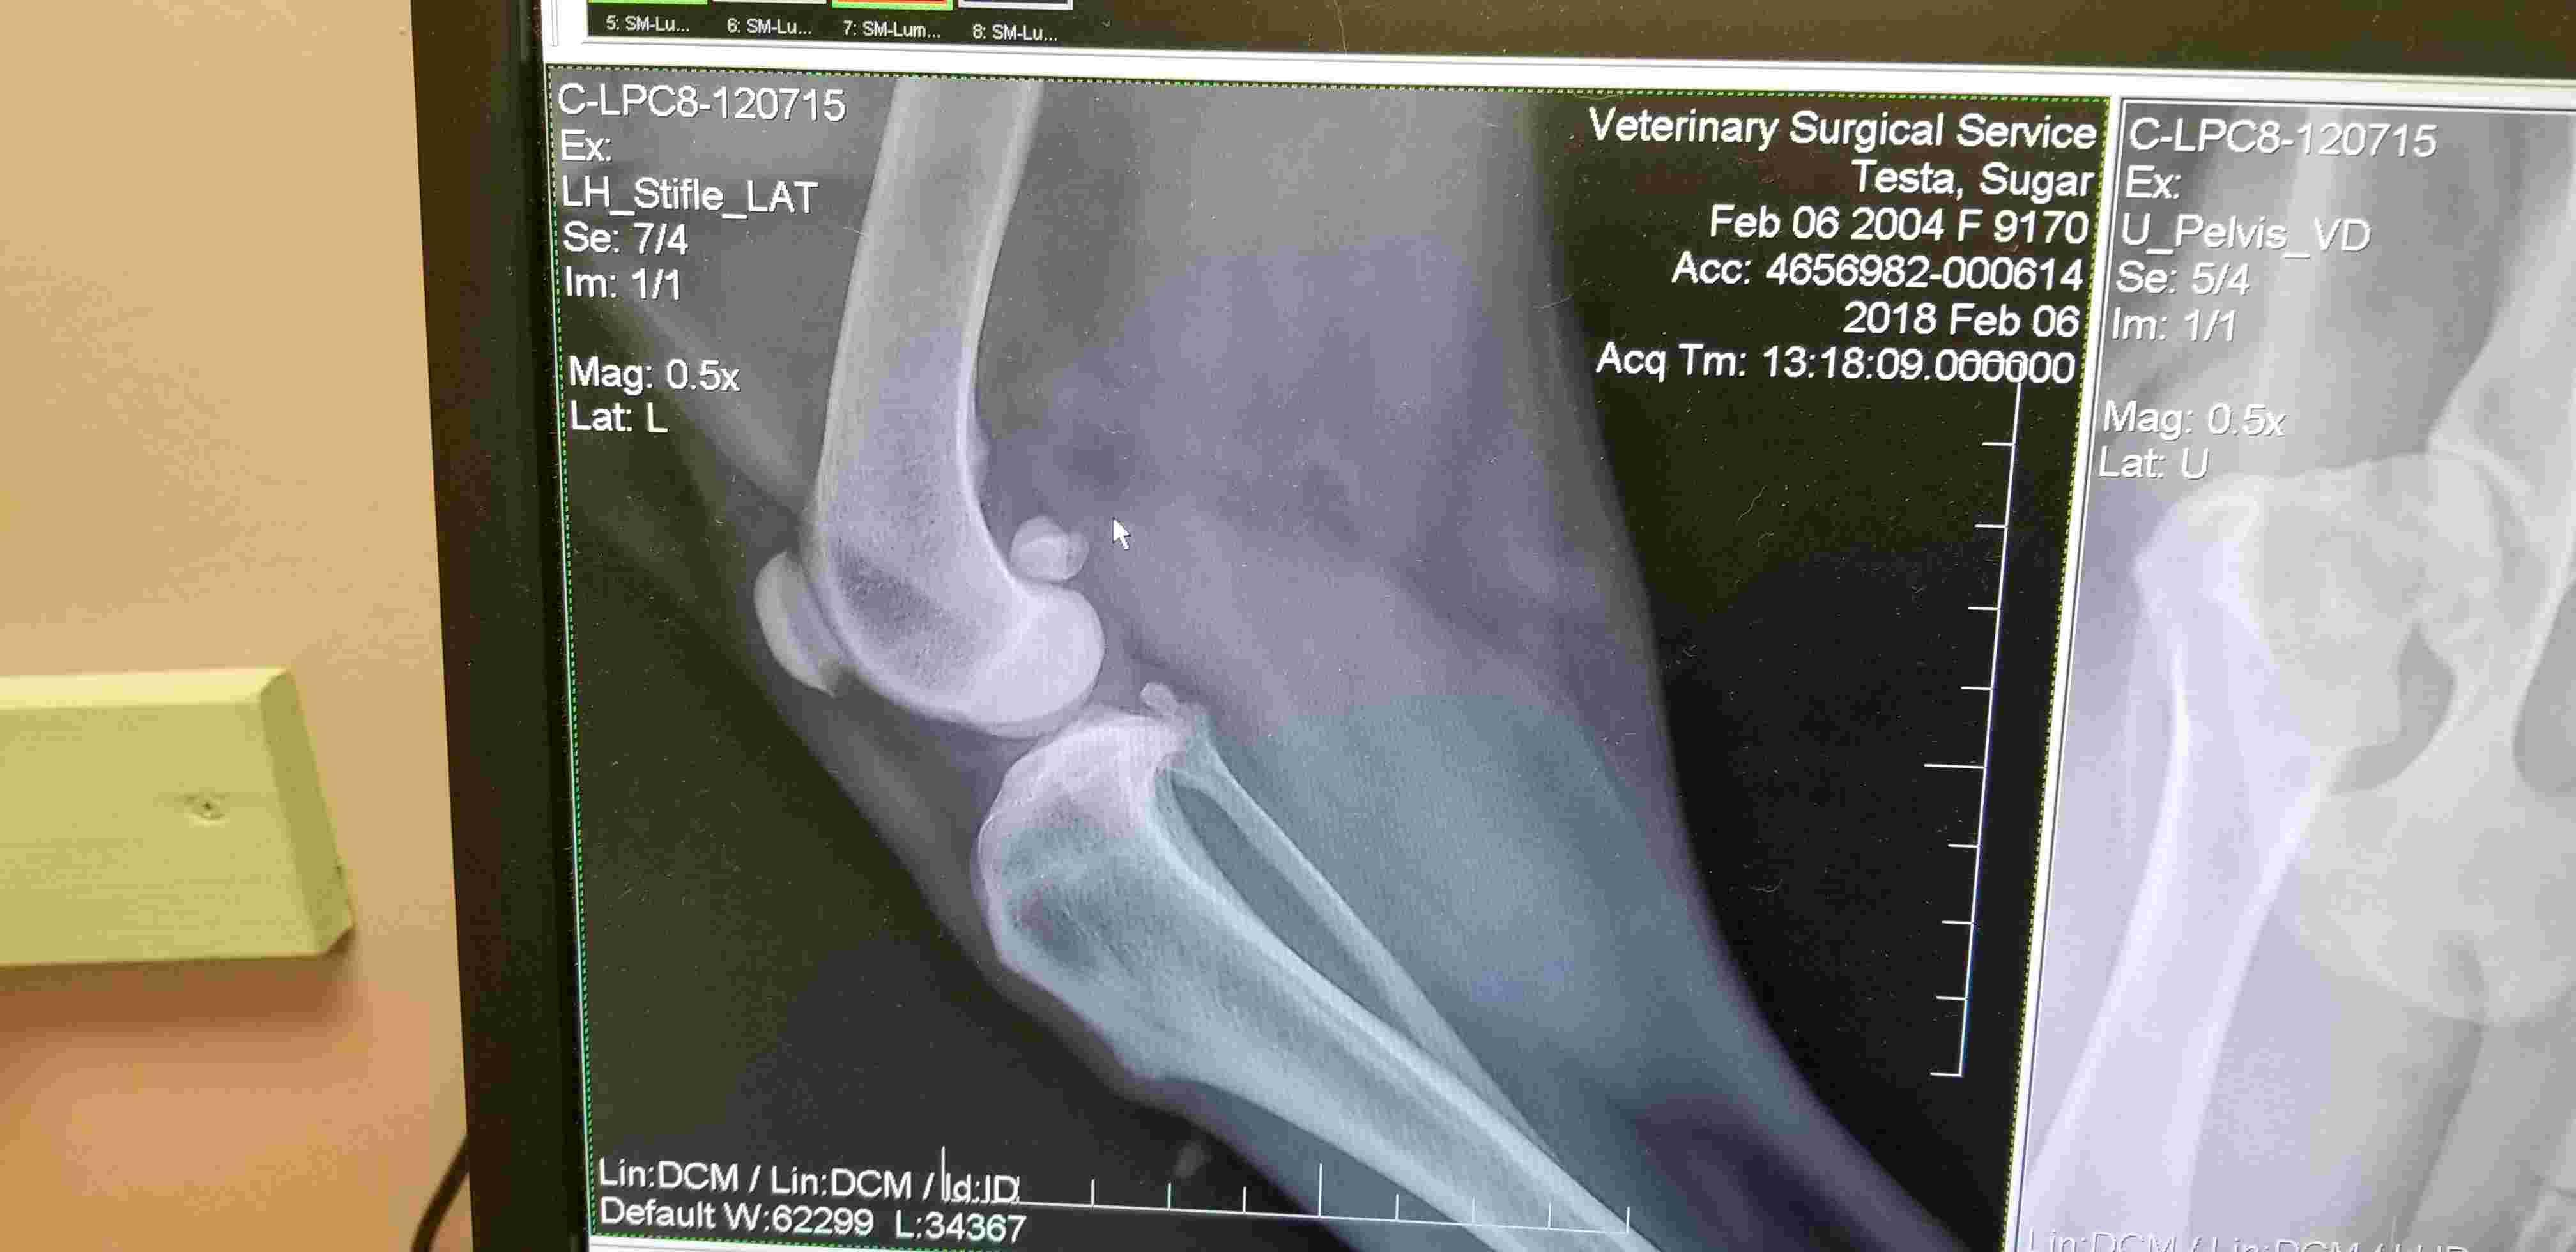

Pet's info: Dog | American Pit Bull Terrier | Female | spayed | 13 years and 8 months old | 45 lbs

Hello. Can you please review my Pitbull's x-rays and see if she has hip dysplasia and/or arthritis? Thanks Joe

Thank you for submitting your question regarding Sugar. She appears to have significant changes to both of her hips indicating severe arthritis. She also appears to have some mild arthritic changes in her left knee. Hip dysplasia is a congenital disorder where the hip joints do not develop properly leading to arthritis later in life. So this is the potential cause of the changes in her hips. I hope she is able to start pain medication to help with her mobility.